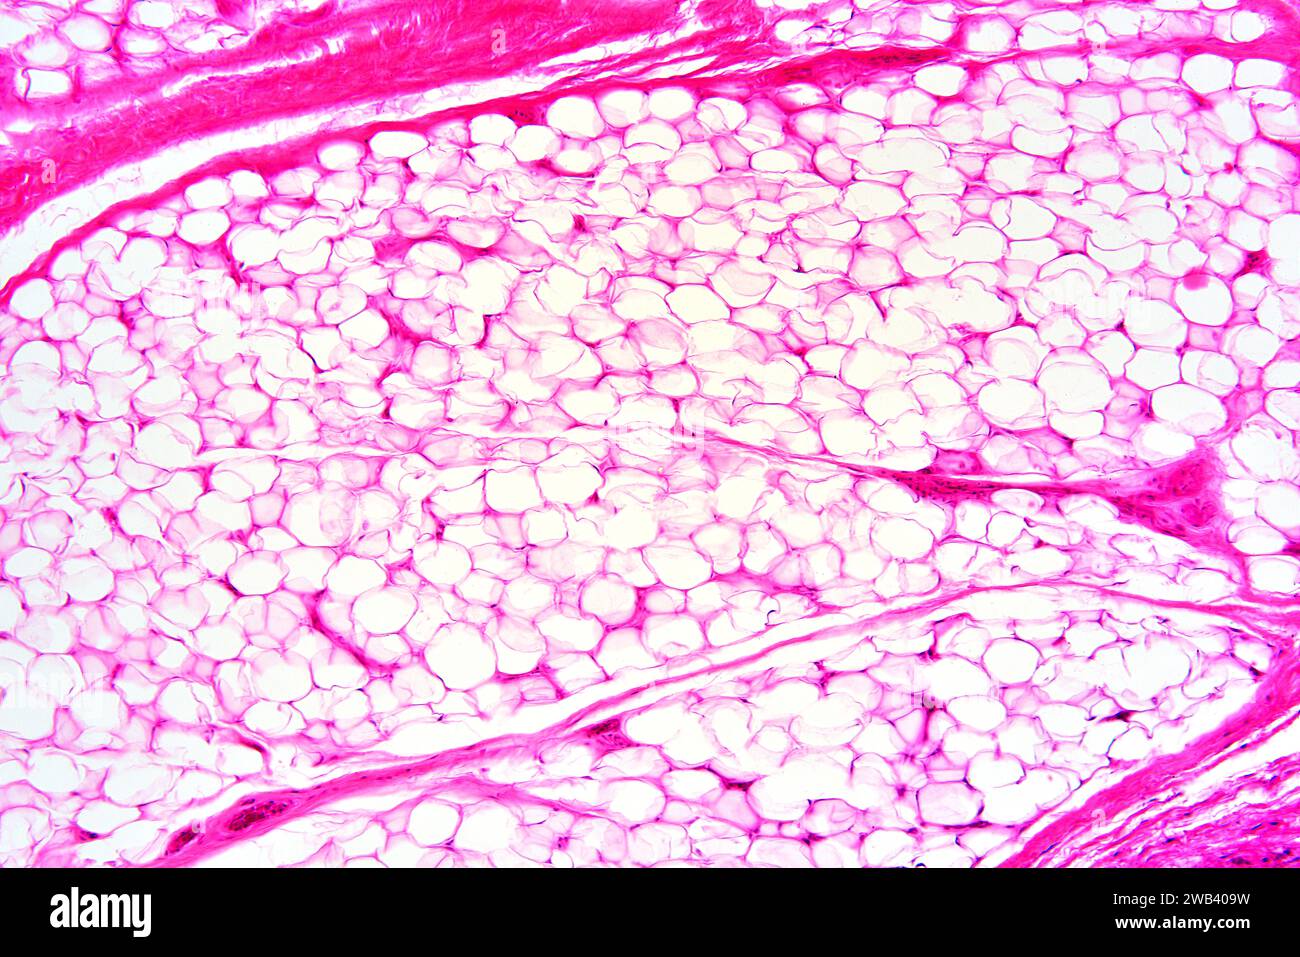

Adipose tissue stock image. Image of eosin, micrograph 117240715 What Type Of Tissue Is Adipose Tissue — adipose tissue is a connective tissue composed of fat cells called adipocytes. — adipose tissue is a type of connective tissue that stores and burns energy. — adipose tissue has historically been classified into two types, white adipose tissue (wat) and brown adipose tissue (bat), which are visibly. White, brown, and beige, which. — adipose. What Type Of Tissue Is Adipose Tissue.

Adipose tissue, light micrograph Stock Image C057/6736 Science What Type Of Tissue Is Adipose Tissue White, brown, and beige, which. Parietal and visceral, and into two types based on structure: — adipose tissue is a type of connective tissue that stores and burns energy. — adipose tissue, connective tissue consisting mainly of fat cells (adipose cells, or adipocytes), specialized to synthesize. It is divided into two types based on location: There are three. What Type Of Tissue Is Adipose Tissue.

Adipose tissue, light micrograph Stock Image C050/6295 Science What Type Of Tissue Is Adipose Tissue — adipose tissue is a type of connective tissue that stores and burns energy. — adipose tissue has historically been classified into two types, white adipose tissue (wat) and brown adipose tissue (bat), which are visibly. White, brown, and beige, which. There are three types of adipocytes: — adipose tissue, connective tissue consisting mainly of fat cells. What Type Of Tissue Is Adipose Tissue.